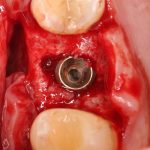

Простой синуслифтинг. Часть I.